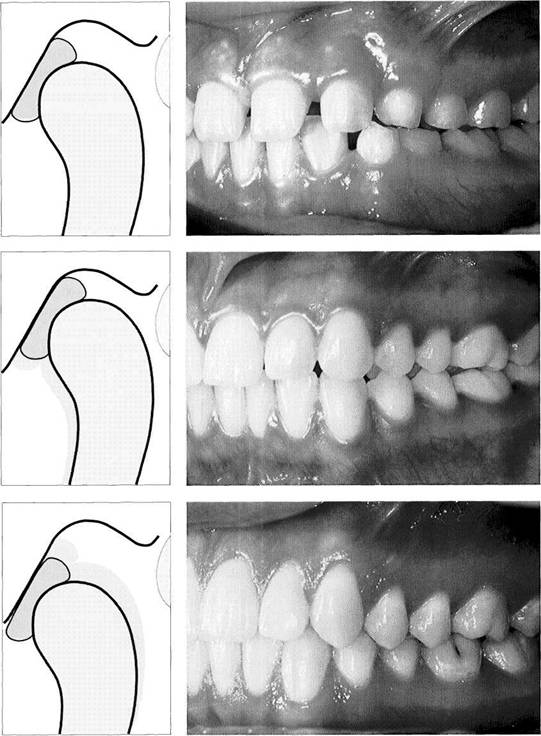

Anatomical Disk Position

Anatomical Disk

Position

In a physiological temporomandibular joint, the pars posterior of the disk lies on the superior portion of the condyle. In the "centric condylar position" the thinnest part of the disk, the pars intermedia, is located between the anterosu-perior convexity of the condyle and the articular protuberance (van Blarcom 1994). This finding is also supported by studies using measurements and mathematical models (Bumann et al. 1997, Kubein-Meesenburg 1985). The pars anterior lies in front of the condyle (Steinhardt 1934, Wright and Moffet 1974, Scapino 1983). The disk is attached to the

medial and lateral poles of the condyle by means of the transversely aligned collagen fibers of the pars anterior and pars posterior. Viewed by itself, this anatomical arrangement with the condyle allows a great degree of movement during active mandibular movements (see p. 46). The disk exhibits viscoelastic properties under compressive loads. Its resistance is strengthened by the arrangement of the collagen fibers (Shengyi and Xu 1991). The elastic fibers within the disk serve primarily to restore the shape of the disk after a load has been removed (Christensen 1975).

Anterosuperior aspect of

the disk-condyle complex

Macroscopic anatomical preparation of a left temporomandibular joint showing the relationship between disk and condyle. The lateral half of the disk has been removed fora clearer view. The dorsal border of the pars posterior is near the region of the apex of the condyle. From a functional point of view, this broad description is not very helpful for diagnostic purposes because the physiological position of the pars posterior depends to a large extent upon the inclination of the protuberance.

Anterolateral aspect

of the

disk-condyle complex

The same preparation in half profile. Here the pars posterior (1), pars intermedia (3), and pars anterior (2) can be clearly distinguished. Although the posterior border of the pars posterior lies over the apex of the condyle, the pars intermedia is in front of the anterosuperior convexity (arrows) of the condyle. The pars anterior is 2.0 mm thick, the pars intermedia 1.0 mm thick, and the pars posterior 2.7 mm thick (Gaa 1988).